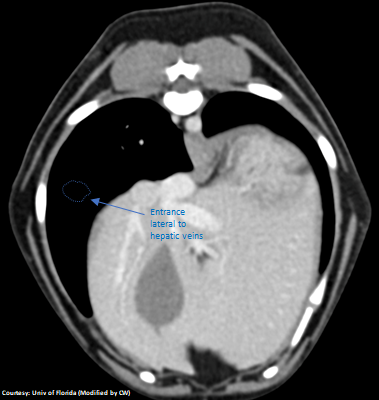

(Caudal Vena Cava Entrance)

“aLGP +RGV”

Aberrant Left Gastro-Phrenic Shunt with Right Gastric Vein contribution

Courtesy: Nihon Univ

Note: “aLGP” rather than “aLGHV” because shunt joins lateral to Left HV